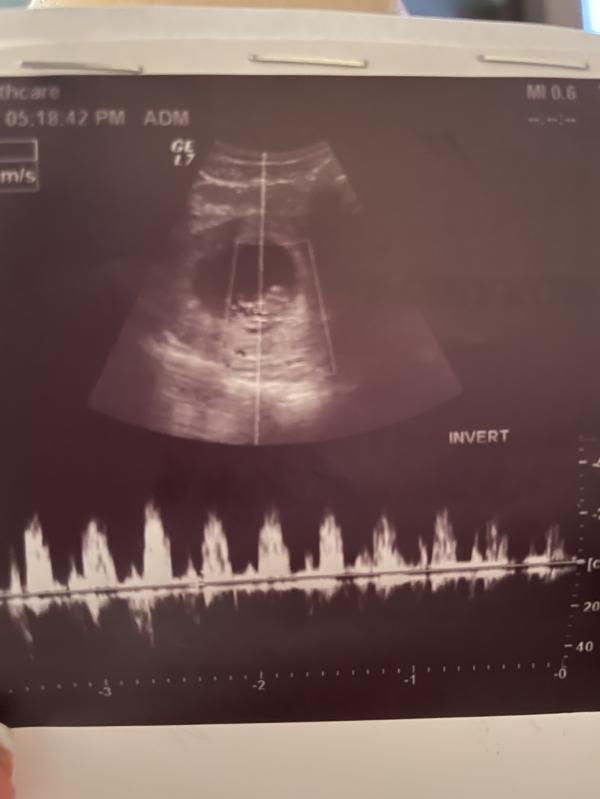

Узи показало, что сердечко бусинки бьется! Когда почувствую шевеления?

Сегодня была на узи

Увидела свою бусинку, сердечко бьется💕 во всю уже шевелится,только я не чувствую🤪